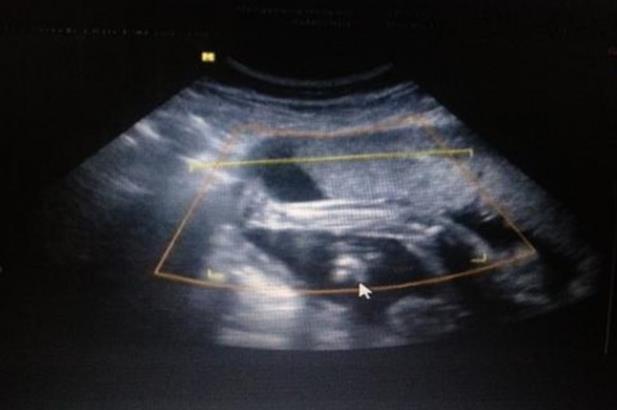

周六一早大姨媽駕到,趕緊預約了周日的試管促排和。今天八點四十到達醫院,打印掛號單,然后到四樓六診室,六診室換了房間,比以前略擠一些。促排第一天,門口遞掛號單和磁卡登記,行程單拿到門外填好,掃夫妻二人行程碼截圖,然后等著護士叫名字。叫到名字錄指紋,交行程單看行程碼,然后拿檔案夾和磁卡給里面桌子護士。我今天不用抽血,只做B超,第一次去,護士讓我上好廁所直接去七診室等著,剛到七診室就喊到我。9:35,B超就做完了。慢悠悠下樓吃了個早飯,回來等11:30聽醫囑。

在試管嬰兒的這個階段,藥物的使用時間是不一樣的,一般要打8-15天左右。例如:1)果納芬(注射用重組人促卵泡激素,需要冷藏):這針比較高級,是一個帶刻度的塑料筆狀,可以根據自己的用量調節好。自醫院帶回家時要用冰袋保溫,回家后立即放入冰箱保鮮。大腹便便;(2)尿促性素(需要冷藏):國產促排藥,價格相對便宜,打屁股。(3)生長激素(需冷藏):這針可自行注射,也可到診所就診。